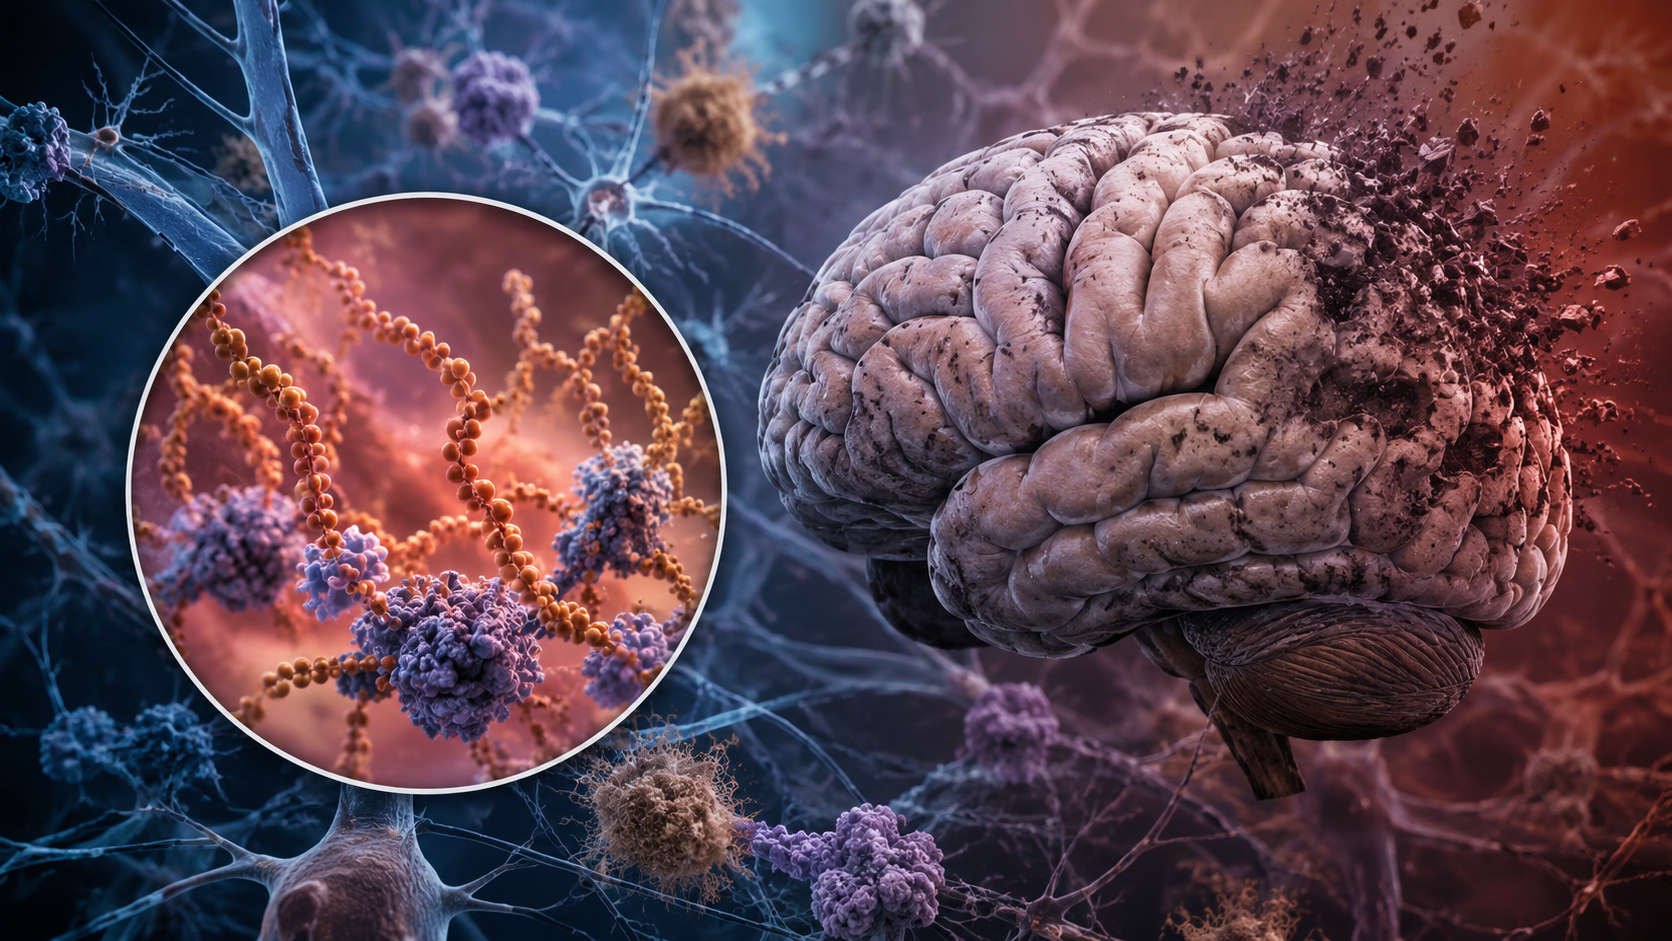

La COVID prolongada, una condición que afecta entre el 5% y el 10% de las personas que se han infectado con el SARS-CoV-2, continúa siendo un enigma médico y científico. Los síntomas, que pueden durar tres meses o más, abarcan desde fatiga y dificultades respiratorias hasta problemas neurológicos y cardiovasculares. Aunque se han propuesto varios mecanismos para explicar este fenómeno, una teoría gana cada vez más peso: la persistencia del virus en el organismo.

Desde los primeros meses de la pandemia, se observó que el SARS-CoV-2, o al menos restos del virus, podría permanecer en diversos tejidos y órganos durante largos períodos. Esto dio origen a la teoría de la «persistencia viral», que sugiere que el virus vivo, o fragmentos residuales del mismo, podría estar detrás de los síntomas prolongados de la COVID.

La diferencia entre virus vivos y fragmentos virales es crucial. Mientras que los restos virales inactivos no generan actividad biológica, los virus vivos pueden seguir replicándose y provocando síntomas. Además, esta persistencia podría ser un caldo de cultivo para nuevas variantes, especialmente en personas con sistemas inmunitarios debilitados.

- Un artículo en Nature reveló que personas con síntomas leves de COVID-19 presentaban eliminación prolongada de material genético del virus, conocido como ARN viral, desde el tracto respiratorio. Aquellos con este desprendimiento persistente tenían un mayor riesgo de desarrollar COVID prolongada.

- Otros estudios detectaron la replicación de ARN y proteínas virales en el fluido sanguíneo años después de la infección inicial, lo que sugiere que el virus podría estar activo en reservorios ocultos, como células sanguíneas o el tracto gastrointestinal.

En conjunto, estas investigaciones refuerzan la hipótesis de que el virus no solo persiste, sino que podría replicarse y perpetuar los síntomas en algunos pacientes.